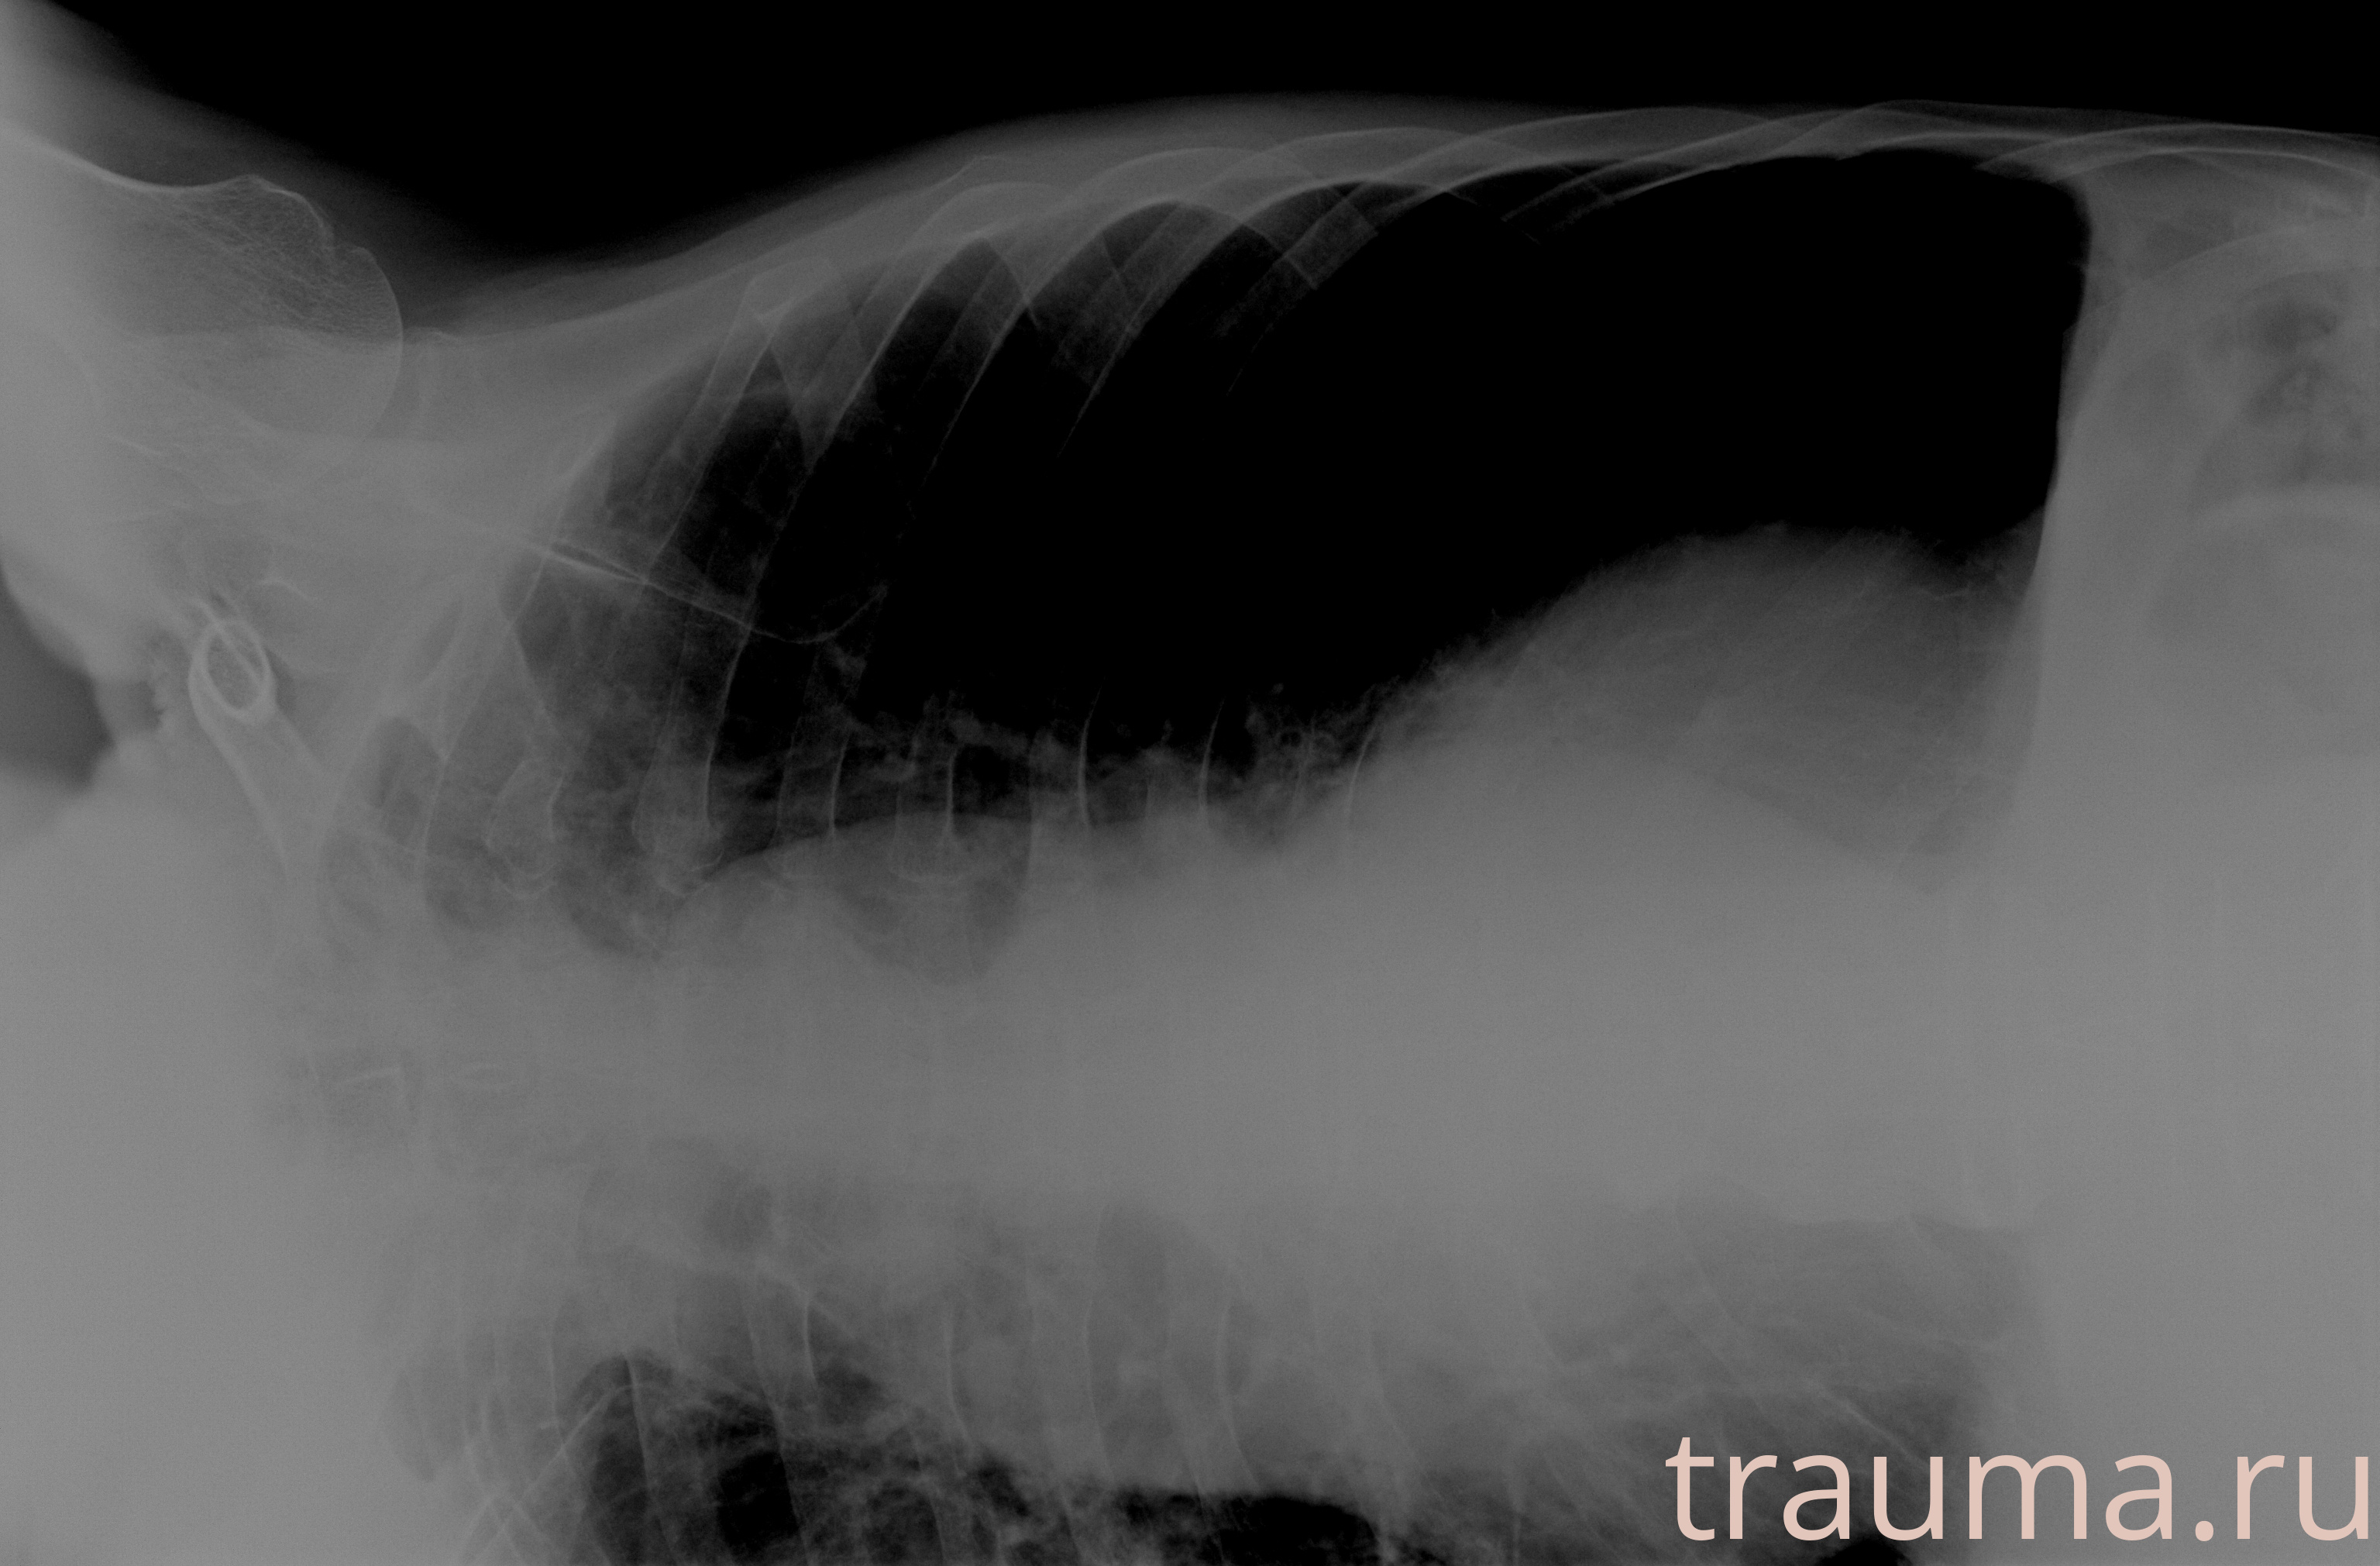

Рентген на дому: по вашему адресу приезжает врач-рентгенолог, травматолог-ортопед с мобильным рентгеновским аппаратом, проводит диагностику травмы или заболевания, делает необходимые рентгенограммы, дает рекомендации по дальнейшему лечению. Получить качественные снимки в домашних условиях возможно благодаря уникальной методике, разработанной МосРентген Центром для института  Склифосовского

при переломе шейки бедра и пневмонии от компании МосРентген Центр - партнера Института имени Склифосовского